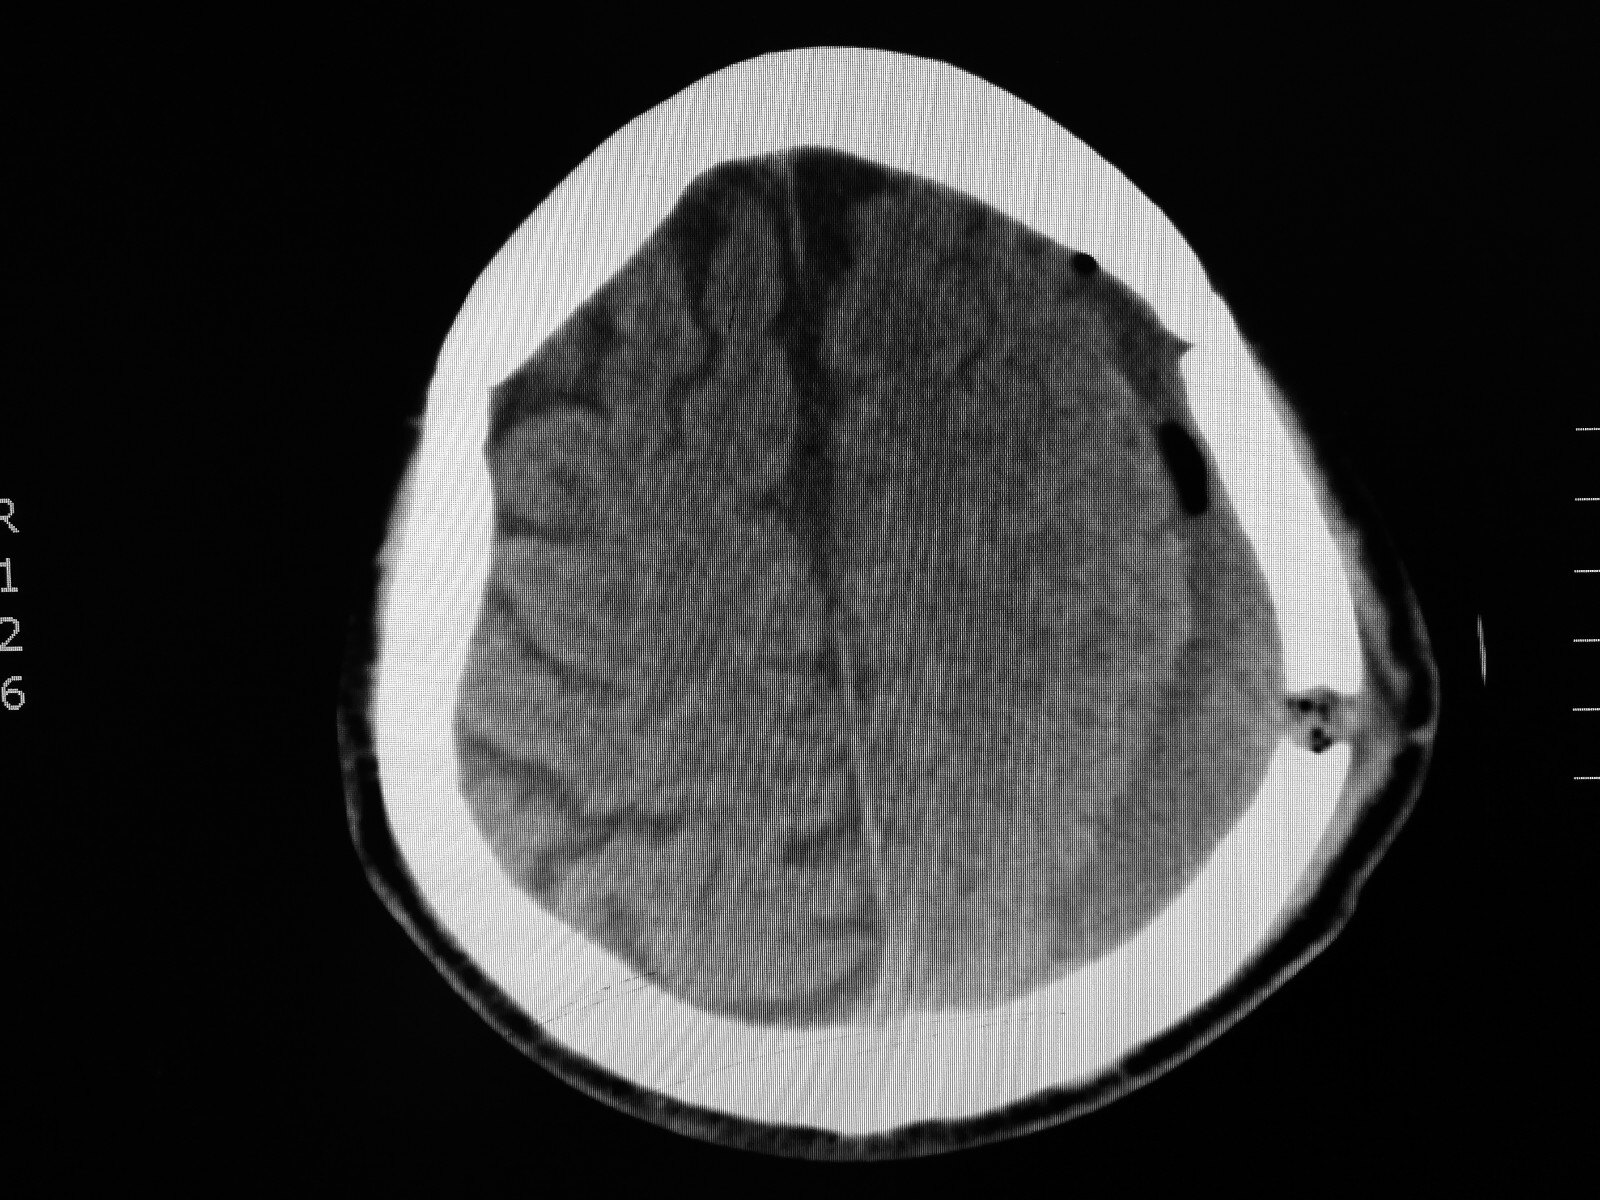

注射碘造影液相对风险较大,所以医生有时候也有顾虑一般急性过敏反应的几率比较多,慢性的也不少,最少需要观察35天中医。